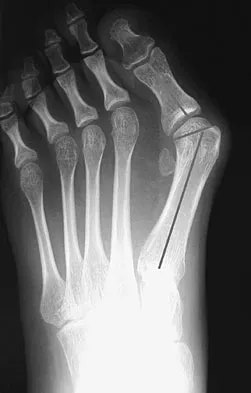

A 47-year-old woman has a right bunion that has been symptomatic despite modifications in shoe wear. She requests surgical correction. An AP radiograph is shown in Figure 37. Treatment should consist of

Because the radiograph reveals an intermetatarsal angle of greater than 15 degrees and an incongruent metatarsophalangeal joint, the treatment of choice is a proximal first metatarsal osteotomy with distal soft-tissue realignment. A distal chevron procedure would not correct this degree of deformity. A Keller procedure is reserved for a less active elderly individual. Arthrodesis is appropriate for a patient with advanced arthritis of the metatarsophalangeal joint. The double osteotomy is reserved for the congruent metatarsophalangeal joint with hallux valgus. Coughlin MJ, Carlson RE: Treatment of hallux valgus with an increased distal metatarsal articular angle: Evaluation of double and triple first ray osteotomies. Foot Ankle Int 1999;20:762-770.